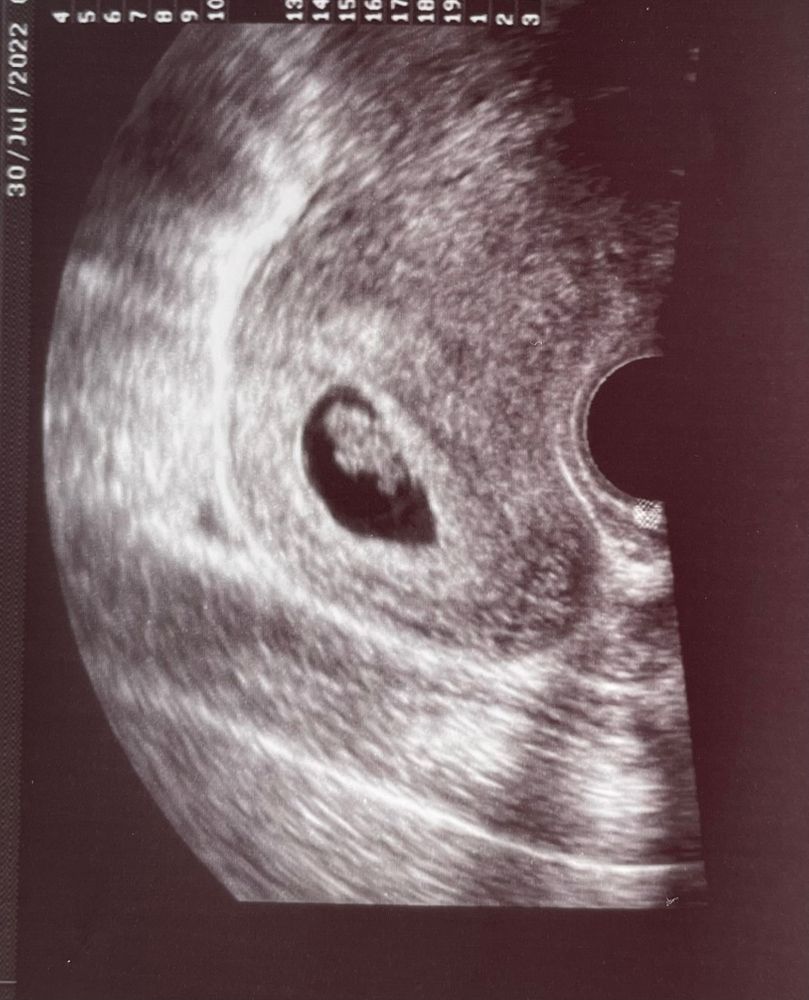

6 недель, отзеркалила.

Так было в оригинале по животу

Подскажите, кто наша креветочка?